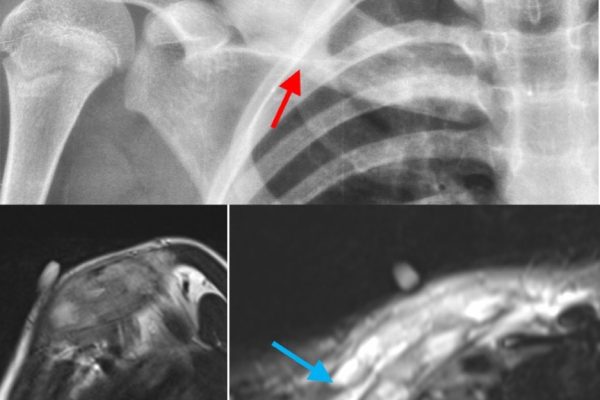

Contrast CT Scan are recommended to provide rich details in the imaging of soft tissues or blood vessels. A few of its applications include:

- Cancer Detection: Highlights tumours and measures their size and spread.